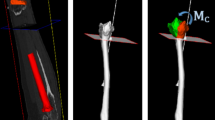

Following 3D analysis based on the mirrored contralateral side, we planned a derotational osteotomy of approximately 15° of the distal radius using additively manufactured surgical guides and a standard distal radius plate (Fig. 5).

The simulation of the postoperative situation using distance mapping revealed that the planned procedure would lead to an overload of the dorsal aspect of the sigmoid notch (Fig. 6).

Based on our simulation, we changed the surgical plan to a derotational osteotomy of the ulna of approximately 15° combined with ulnar shortening using intraoperative guides and a standard ulna locking plate of 2.8 mm (Medartis AG, Basel, Switzerland) (Figs. 7, 8).

Based on correctly segmented data, distance mapping allows for noninvasive quantification of articular congruency, joint space width, cartilage thickness and interactions of the joints. We used static distance mapping, which was generated by certified software. The visualization of the pre- and postoperative condition in our first case allowed us to simulate the resulting biomechanics of the planned intervention. Based on this information, we changed our surgical plan and avoided a potentially harmful osteotomy of the distal radius and addressed the ulna instead.